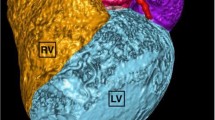

Cardiac MRI interpretation and offline post-processing analysis (CVI42, Circle Cardiovascular Imaging, Calgary, Canada) of ventricular ejection fractions was performed by consensus between two fellowship trained cardiovascular radiologists. Ventricular ejection fraction calculations were performed by manual contouring of the endocardial border of both ventricles during both end-diastole and end-systole utilizing all relevant sequences of the short axis series. Offline post-processing analysis also calculated end diastolic, end systolic, and stroke volumes of both ventricles. The results of the original studies were collected retrospectively, and were not reinterpreted.

The mean RVEF using cardiac MRI was 28.3% (median 27.0%, range: 16 – 43%). The mean RVEF calculated using FPRNA was 32.6% (median 32.0%, range: 9 – 56%). The mean LVEF calculated using cardiac MRI was 20.7% (median 21.0%, range: 12 – 40%), and mean LVEF calculated using MUGA was 22.6% (median 19.0%, range: 12 – 49%).